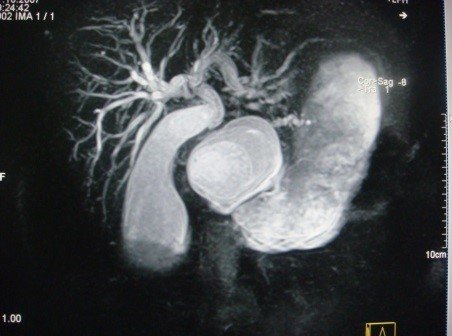

- Kontrastlı KT və ya MRT standart müayinədir, şişi və yayılma dərəcəsini müəyyənləşdirilməsində önəmlidir.

- Görüntüləmdə: erkən arterial fazada contrast tutan və venoz fazada yuyulan, MRT-də hipointens, ətraf toxumalara invaziv, böyüməyə meylli, baş nahiyyəsində yerləşərək xoledoxu və pankreatik axacağı genişləndirən (“iki axacaq simptomu”) törəmə

- Kontrastlı KT/MRT (5 mm-lik kəsiklərlə aparılan kontrastlı KT/MRT 50 – 60% həssaslıq göstərir.